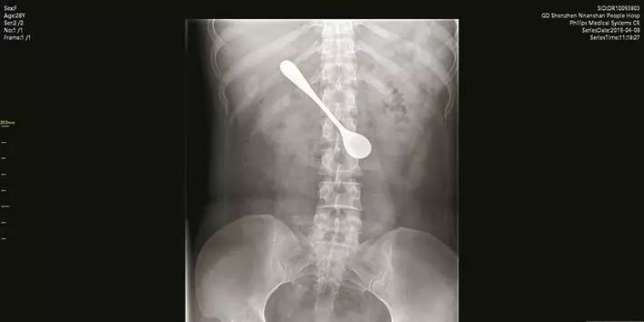

Foto rontgen Xu (Foto: Apple Daily)

Resah dengan peristiwa yang dia alami, Xu pergi ke dokter. Setelah dilakukan X-Ray, AirPod tersebut terlihat di dalam sistem pencernaan Xu.

Ketika tiba di Rumah Sakit Shenzhen Nanshan pada hari Senin kemarin, dokter menganjurkan Lily untuk melakukan rontgen.

Dokter terkejut setelah melihat hasil rontgen dan menemukan sendok itu sudah tersangkut di dalam ususnya.

Repotnya, sendok tersebut tersangkut dalam posisi melintang hingga doktersedikit kesulitan untuk mengeluarkannya.

" Karena berada dalam posisi agak horizontal, kami harus membalik sendok secara vertikal secara hati-hati sebelum menariknya keluar," kata Dr Sun Tingji kepada Pear Video.

Dokter Sun mengatakan meski Lily mengaku tidak merasakan sakit, tapi sendok itu telah menyebabkan pembengkakan dan pengikisan di dalam ususnya.